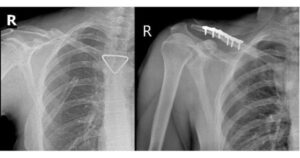

Trong nước, với đào tạo y khoa, AI được ứng dụng hiệu quả tại một số trường đại học trong nước; sinh viên và bác sĩ thực hành được đào tạo cách sử dụng và kiểm tra kết quả từ các phần mềm AI hỗ trợ chẩn đoán hình ảnh (ví dụ: phát hiện ung thư, tổn thương phổi trên CT/X-quang) để nâng cao khả năng đọc và ra quyết định lâm sàng.